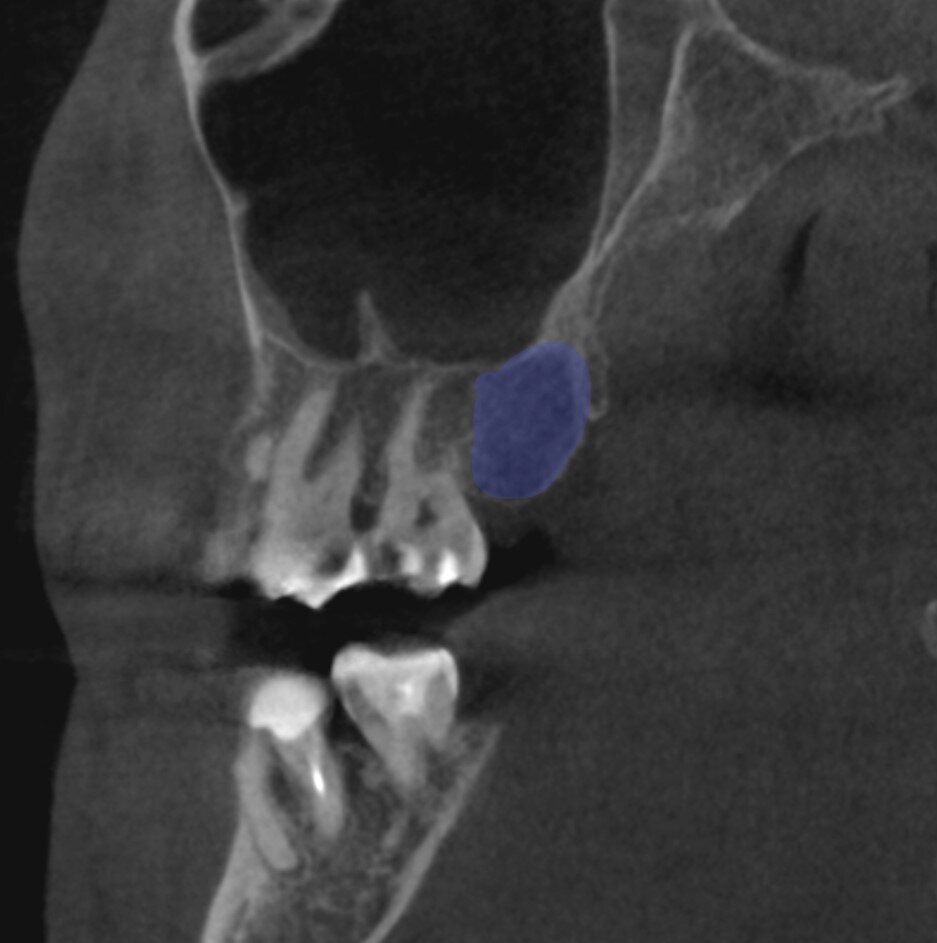

Прошло почти 7 месяцев и время оценить полученный результат - пациентка из другого города прислала нам снимок КЛКТ:

Ничего не понятно? Правильно, этот снимок для продвинутых подписчиков)

И листайте фото, что бы понять объём полученной кости в цифрах:

Как видно - кости даже чуть больше, чем требовалось. Но лучше больше, чем меньше, 100%.